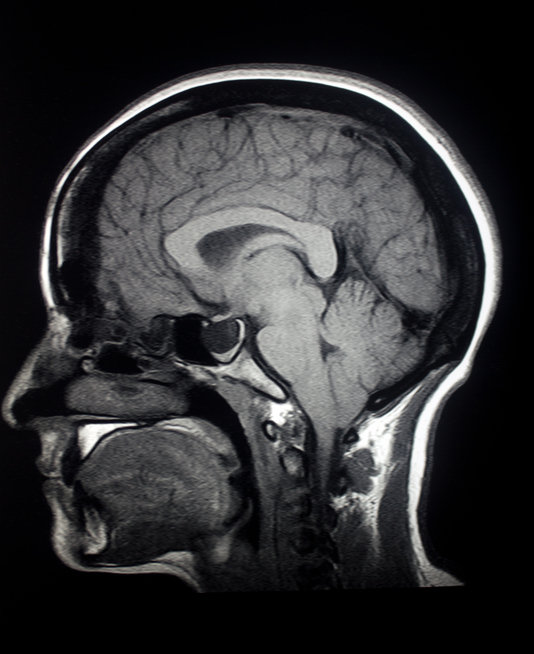

치매의 가장 흔한 형태인 알츠하이머병에 걸릴 위험은 여성이 남성보다 약 두 배 더 높다. 그런데 전반적인 뇌 위축 속도는 오히려 남성이 더 빠르다는 연구 결과가 나왔다. 이는 나이 관련 뇌 위축에서 나타나는 성별 차이가 여성의 높은 알츠하이머병 진단 비율을 설명하기 어렵다는 것을 보여준다.

노르웨이 오슬로 대학교 연구진이 주도해 미국 국립과학원 회보(PNAS)에 발표한 이번 연구는 17세에서 95세 사이 건강한 남녀 4726명을 대상으로 평균 3년 간격으로 촬영한 1만 2638건의 뇌 MRI 데이터를 분석했다.

연구 결과, 남성은 나이가 들수록 여성에 비해 뇌의 더 많은 영역에서 피질 두께와 표면적이 감소하며, 노년기에는 기저핵 등 피질하 구조에서도 위축이 관찰됐다. 반면 여성은 몇몇 특정 영역에서만 감소가 나타났으며, 고령에서는 뇌실 확장이 두드러졌다. 뇌실은 뇌 척수액이 흐르는 뇌 속 공간으로, 뇌 조직이 쪼그라들면서 상대적으로 뇌실이 넓어지는 현상을 의미한다.

주목할 점은 회색질, 백색질, 대뇌 피질의 감소 속도에서 남성이 여성보다 더 빠른 경향을 보였다는 것이다. 이들 영역은 기억, 학습, 사고력 등 인지 기능과 밀접하게 관련이 있으며, 알츠하이머병에서 중요한 손상 부위로 알려져 있다.